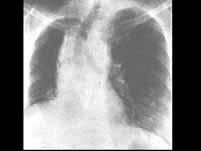

问题 急性放射性肺炎可发生在开始放疗后_______内,多数发生在放疗后________内()

选项 A.3个月,6个月 B.1个月,3个月 C.3个月,6个月 D.半个月,3个月 E.3个月,3个月

答案 B